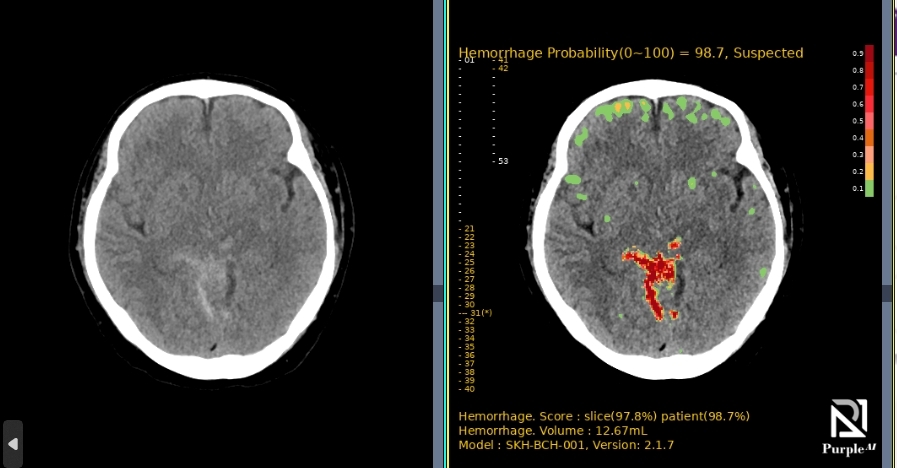

AI-powered diagnostic support for rapid, accurate detection and localization of brain hemorrhages on non-contrast CT, with ROI visualization and volume quantification to help radiologists assess hemorrhagic regions.

A multi-center, randomized, retrospective crossover superiority pivotal study, demonstrating high performance across all major ICH subtypes.

| Trial Size | 394 brain CT images (198 positive / 196 negative cases) |

| AUC | 98.64% |

| Sensitivity | 95.45% |

| Specificity | 98.47% |

| Speed (Notification Seconds) | Average time was 16.39 ± 5.46 seconds |

| Subtype Performance | 94.7%~100% |